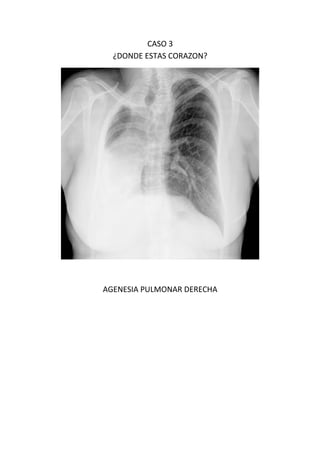

Este documento presenta 7 casos de patología torácica que serán discutidos en una sesión de interpretación radiológica. El objetivo es que los asistentes tomen notas aclaratorias durante la discusión interactiva de cada caso, en lugar de una mera explicación teórica. Los casos incluyen agenesia pulmonar derecha, situs inversus, estridor, neumonía con hemoptisis y enfermedad intersticial. El último caso involucra a un paciente de 86 años con tos y disnea que podría tener una consolidación en la base